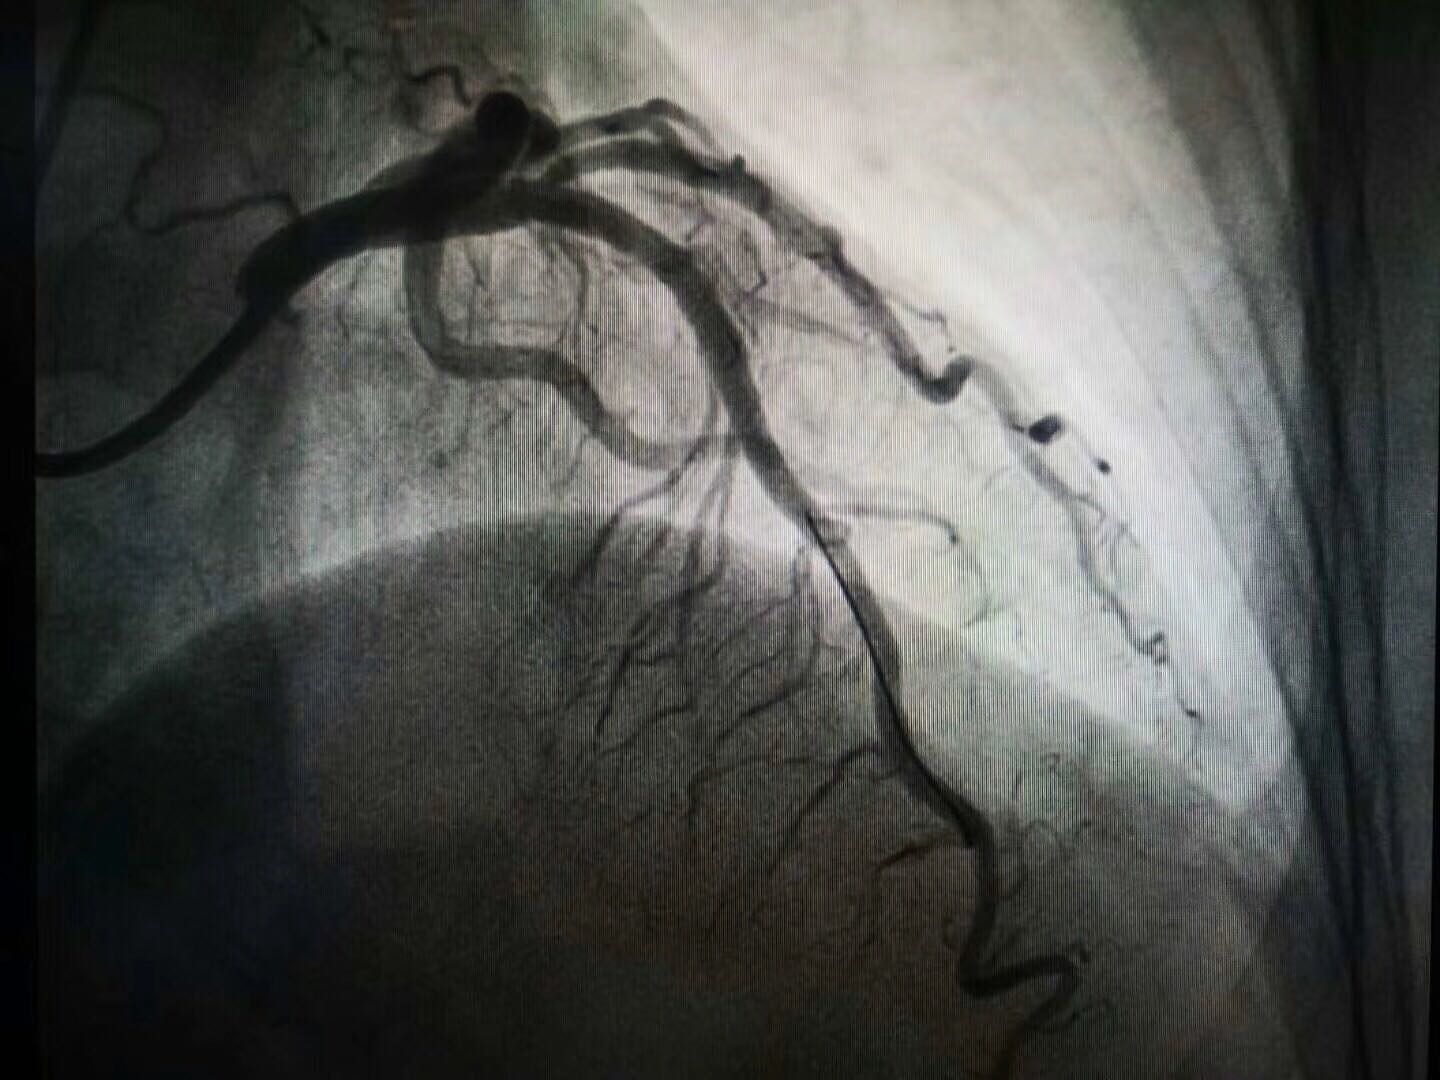

该患者为女性,年龄64岁,患者因“不稳定性心绞痛”多次就诊,饱受病痛折磨。本次就诊我院后,完善冠状动脉造影示LAD近段80%重度狭窄,在副院长白锋带领下,治疗团队严格把握适应症,和患者反复沟通后,最终于病变处成功植入3.5*21mmNeoVas生物可吸收支架,手术准备充分,术中严格执行PSP技术,术后经IVUS证实支架释放完美。生物可吸收支架是目前全球的研究热点,给冠心病患者治疗带来了新希望,避免金属植入物永存体内,恢复血管舒缩功能,避免金属牢笼禁锢,利于再次介入治疗,实现从“血管再通”到“血管再造”的新蜕变。